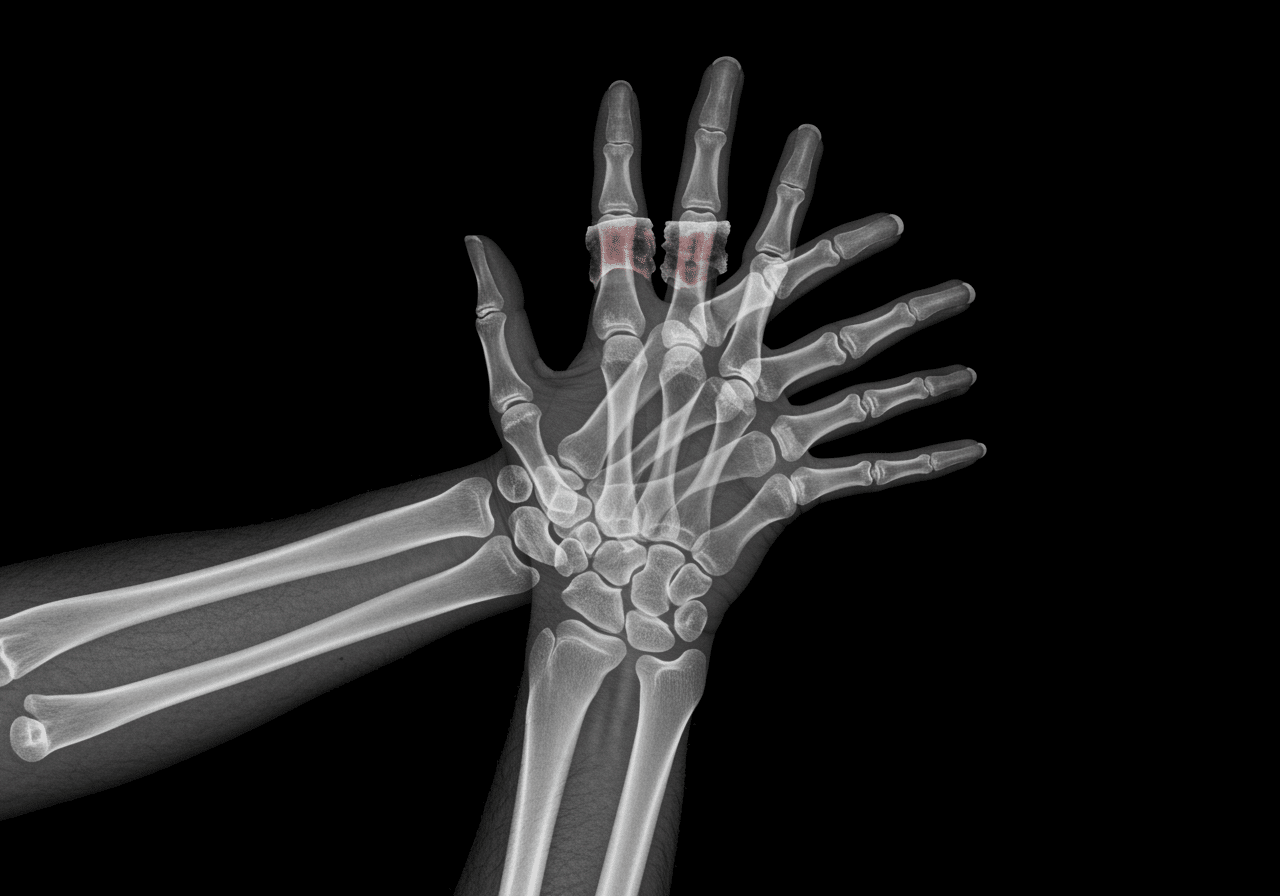

Unlike traditional urgent care centers that lack complex fracture reduction capabilities or close at 8 PM, Priority ER operates 24/7 emergency services with immediate access to digital x-ray imaging, emergency splinting techniques, and board-certified physician-performed fracture reduction within the critical first hour. Our COLA-certified diagnostic imaging[4] ensures accurate fracture identification while our direct hand surgeon consultation ensures seamless coordination when surgical fixation becomes necessary for complex intra-articular fractures or tendon injuries.

Hand Fracture Treatment Process at Priority ER: Zero Wait Orthopedic Care

Advanced imaging through our comprehensive diagnostic capabilities provides scaphoid-specific views, oblique projections identifying fifth metacarpal fractures, and true lateral wrist views assessing lunate alignment that standard PA/lateral views cannot fully visualize. For pediatric cases, our emergency physicians employ specialized growth plate assessment using Salter-Harris classification preventing physeal arrest and angular deformity that improper classification causes. This comprehensive approach explains why the American Society for Surgery of the Hand recommends emergency departments over urgent care for all displaced hand fractures, scaphoid fractures, or open wounds requiring comprehensive evaluation and specialized immobilization unavailable in limited-capability urgent care settings.